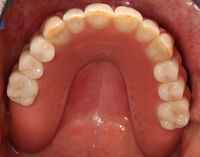

Die Ausgangssituation (Abb.1, Abb.2, Abb.3 ) zeigt einen im Oberkiefer zahnlosen (Abb.4) und im Unterkiefer mit zwei Restzähnen bezahnten Patienten (Abb.5). Der Patient leidet sehr stark unter dem fehlenden Halt der nicht mehr richtig sitzenden Oberkiefer- und Unterkieferprothesen. Diese führen für den Patienten zu einer stark verminderten Lebensqualität, da sowohl die Essensaufnahme, als auch die soziale Interaktion mit den Mitmenschen stark beeinträchtigt ist. Aufgrund des stark zurückgegangenen Knochenniveaus und dem damit verbundenen schlechten Prothesenlager, ist eine wirkliche Verbesserung der Gesamtsituation nur über zusätzliche Befestigung der Prothesen über im Knochen fixierte Zahnimplantate denkbar. Aufgrund des starken Knochenrückgangs sowohl im Ober- als auch im Unterkiefer, ist das Einbringen von Titan-Zahnimplantaten zur Stabilisierung der Prothesen nicht ohne aufwändigen Knochenaufbau möglich. Hierzu ist der Knochen den man innerhalb der Mundhöhle gewinnen kann nicht ausreichend und so bietet sich die Knochenentnahme im Bereich des Beckenkamms an.

Damit stellt man sicher, dass die Implantate hinterher auch an der richtigen Position stehen und den späteren Zahnersatz optimal unterstützen (Abb.11). Abschließend erfolgt die prothetische Versorgung des Patienten. Dazu werden die Implantate im Mund abgeformt (Abb.12) und mit Hilfe einer „Abformung“ auf ein Gipsmodell übertragen (Abb.13). Auf diesem wird anschließend die prothetische Versorgung hergestellt (Abb.14). In diesem speziellen Fall wurde für den Oberkiefer eine steggetragene Prothese (Abb.15, Abb.16) hergestellt. Dieser wird dann auf den Implantaten im Mund verschraubt (Abb.15) und darüber eine herausnehmbare Prothese (Abb.17) verankert (Abb.16).